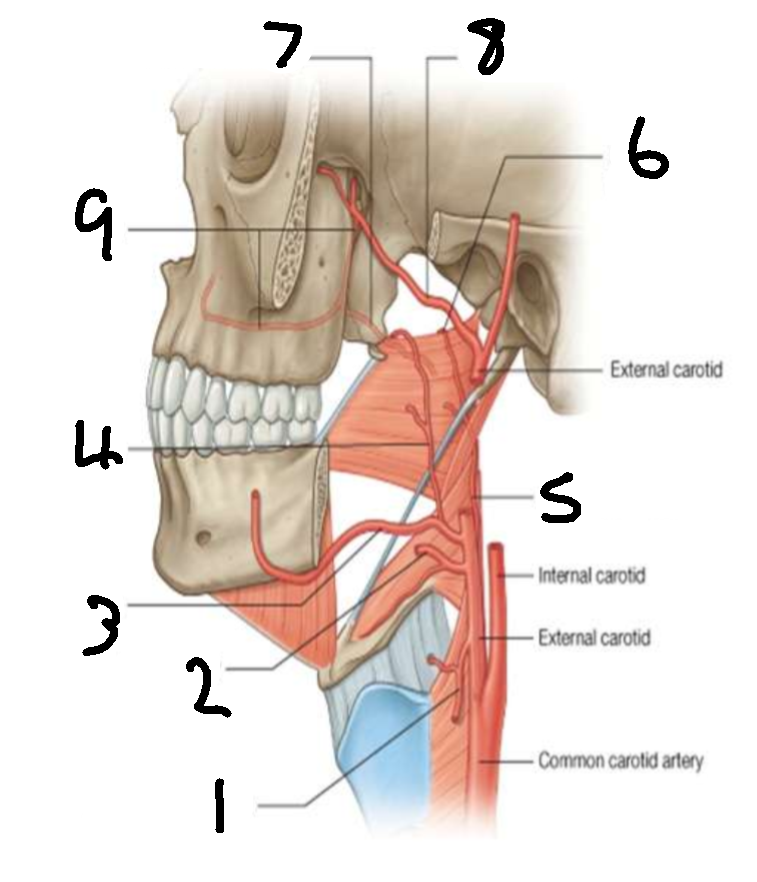

What is 1?

superior thyroid artery

What is 2?

lingual artery

What is 3?

facial artery

What is 4?

ascending palatine artery

What is 5?

ascending pharyngeal artery

What is 6?

palatine branch of pharyngeal artery

What is 7?

lesser palatine artery

What is 8?

maxillary artery

What is 9?

greater palatine artery